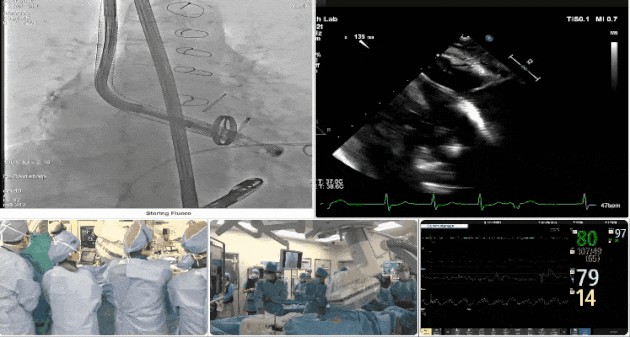

第三例患者手術(shù)難點

1、心率慢(<50bpm),術(shù)后起搏器植入風(fēng)險,術(shù)前需評估心電圖情況;2、CT顯示主動脈瓣機械瓣置換術(shù)后,需明確三尖瓣是否同期做過修復(fù)。

術(shù)中TEE觀察夾持件的位置

術(shù)后DSA

術(shù)后超聲評估瓣膜穩(wěn)定性良好,無瓣周漏

手術(shù)過程

術(shù)者采用經(jīng)右側(cè)頸靜脈入路的方式將輸送器送入患者心臟內(nèi),在TEE及DSA引導(dǎo)下調(diào)整輸送器頭端角度,使得輸送器與三尖瓣瓣環(huán)平面垂直。在輸送器進入右心室后釋放室間隔錨定裝置,而后釋放瓣葉夾持件(2個耳片結(jié)構(gòu))成垂直狀態(tài)。在TEE及DSA確定夾持件固定至三尖瓣葉根部且位于右室側(cè)后釋放人工瓣心房側(cè)盤片。隨后調(diào)整瓣膜同軸性以及室間隔錨定件位置(貼合室間隔),前推藏針管并固定,進而釋放室間隔錨定裝置,并再次確認(rèn)瓣膜位置、穩(wěn)定性及同軸性,合攏輸送鞘后撤出輸送器,最終順利完成LuX-Valve Plus人工三尖瓣瓣膜的植入。